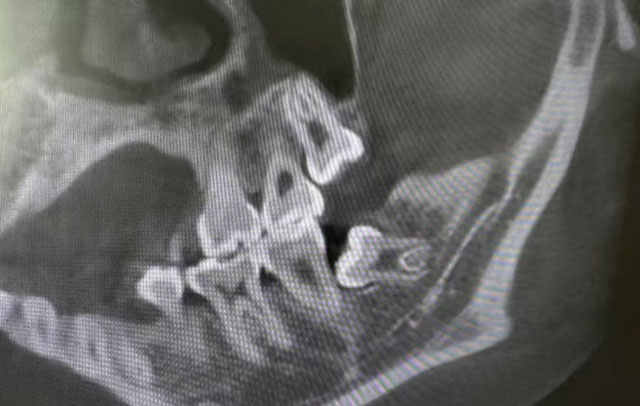

总结来说,一个人长不长智齿都是正常的,只长1颗或长全4颗也都有可能。那么问题来了,很多人其实是不知道自己有几颗智齿的,因为一些智齿并不会完整萌出,有些甚至完全埋伏在牙槽骨里,需要拍片才能发现。

先说6号牙,它是最早长出来的恒磨牙,是人一生中使用时间最长的磨牙。小朋友或家长没有做好清洁的话,非常容易龋坏,严重龋坏后到了成年阶段就容易形成缺损和缺失。至于7号牙,可能并不是自身的问题,它的龋坏、缺损和缺失往往和8号牙有关,是由“隔壁”长得不正的智齿一手造成。位置不正的智齿,不管是完全萌出、部分萌出还是以埋伏阻生的姿态“潜伏”在牙槽骨里,对7号牙来说都是隐患。